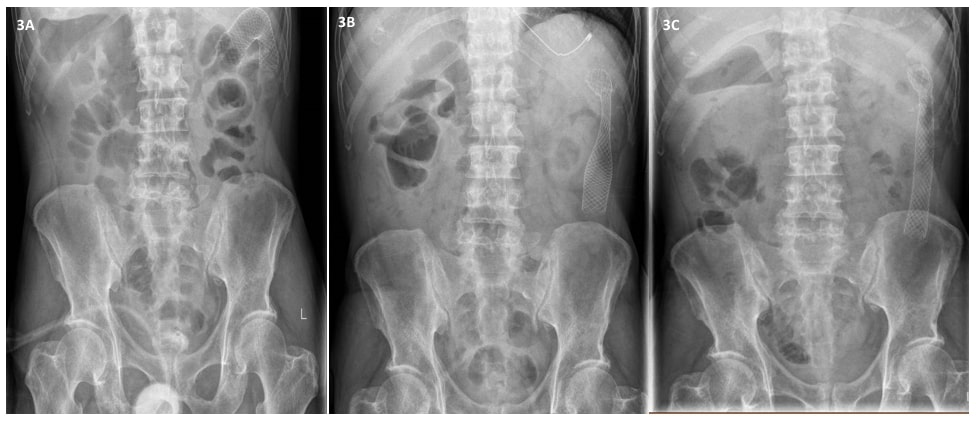

1例老年男性因上腹绞痛1周,伴非胆汁性呕吐和非血性腹泻就诊。患者有高血压、2型糖尿病、慢性酒精中毒伴复发性胰腺炎和长期正色性正常红细胞性贫血病史。显示上腹部压痛,无其他腹膜炎体征。显示白细胞计数正常,为8.17 x 103/µl(正常范围4-11 x 103/µl),肝功能检查正常。脂肪酶为81 U/L(正常范围24-151 U/L),血清癌胚抗原(CEA)为4.9 U/L(正常范围<3 U/L)。图1显示了腹部和骨盆CT扫描的结果。

腹部和盆腔CT显示脾曲周围有一段环周狭窄伴壁增厚、肠袢近端扩张和慢性胰腺炎特征(图1A-C)。鉴于CEA升高和贫血,初步判断是由脾曲恶性肿瘤引起的肠梗阻。因此对患者行内镜下支架置入术(图2A-B)。但发生了早期支架移位(图3A-C),这种情况非常罕见。因此,患者在内镜下支架置入术后6天行早期腹腔镜下左半结肠切除术,以切除梗阻病变,防止支架移位造成再梗阻。